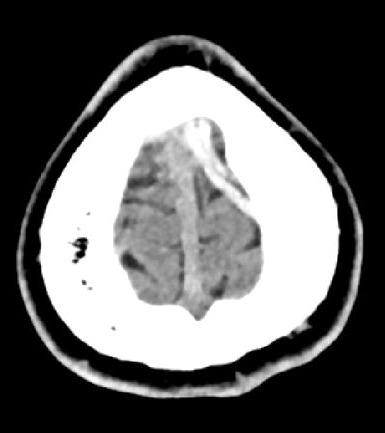

Huit jours plus tard, le patient présente un épisode de clonies du membre supérieur droit, suivi, dans la journée, d’une crise tonico-clonique généralisée, sans céphalées, nausées ni vomissements. Il s’agit du premier épisode décrit chez ce patient. Le scanner cérébral non injecté révèle une hyperdensité au niveau de la veine corticale de la convexité frontale postérieure gauche (fig. 1). L’angioscanner confirme une thrombose veineuse cérébrale (TVC), sans hémorragie ni atteinte parenchymateuse associée (fig. 2). Une relecture de l’IRM confirme l’absence d’antériorité ou de signe qui aurait pu être annonciateur d’une TVC.

L’imagerie permet de poser le diagnostic. Le scanner non injecté peut mettre en évidence des signes directs tels que l’hyperdensité spontanée d’un caillot (signe de la corde). Néanmoins, ce signe n’a pas une spécificité élevé, puisqu’il est aussi observé chez des patients atteints de polyglobulie, chez le sujet jeune avec un hématocrite élevé ou chez le ­patient déshydraté.5 L’angioscanner met en évidence un ­défaut de remplissage après injection (signe du delta vide quand le caillot est au niveau sinusal).4 L’IRM constitue l’examen de référence, en particulier pour les formes corticales et les atteintes parenchymateuses.2